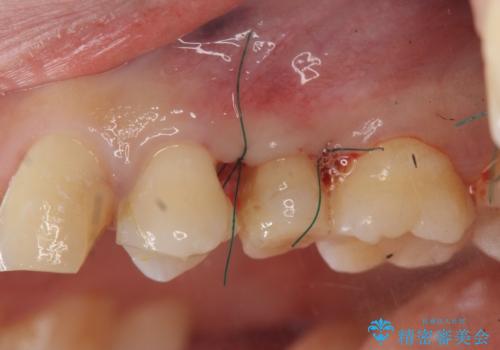

挺出小矯正を行った縁下カリエス治療

X線撮影を行い、隣接面に多発した虫歯と歯ぐきよりも深くなってしまった虫歯を小矯正をおこなったのちのセラミック治療で問題を解決します。

小矯正を行い深い虫歯を改善した後は、小手術を行うことで歯ぐき・周囲歯槽骨の状態を整えることでより安定した歯周環境を得ることができます。